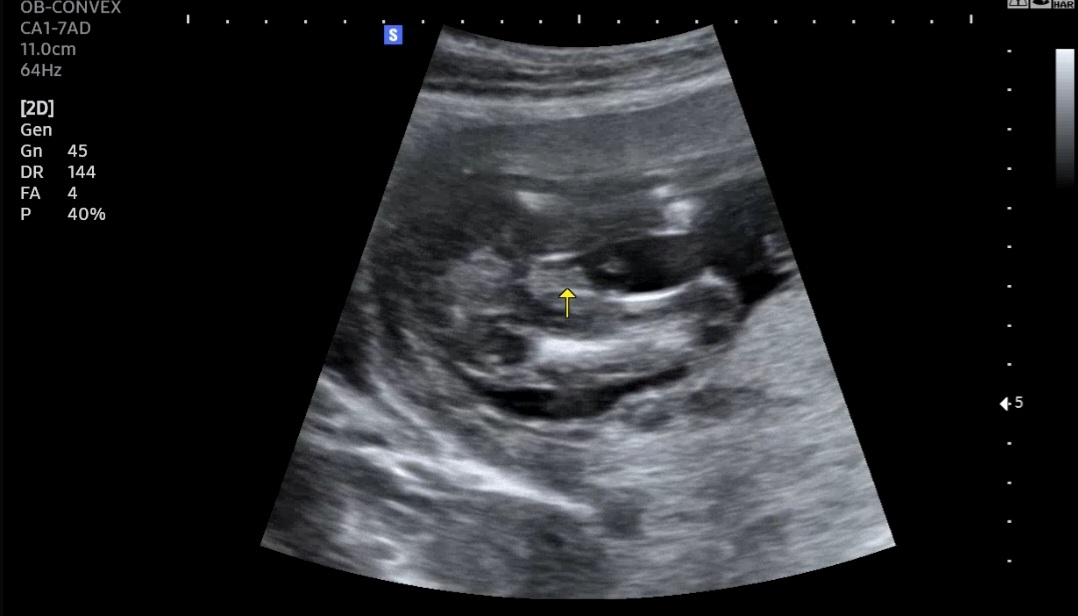

더 볼것도 없이 남아죠?

ㅎ 남아죠?